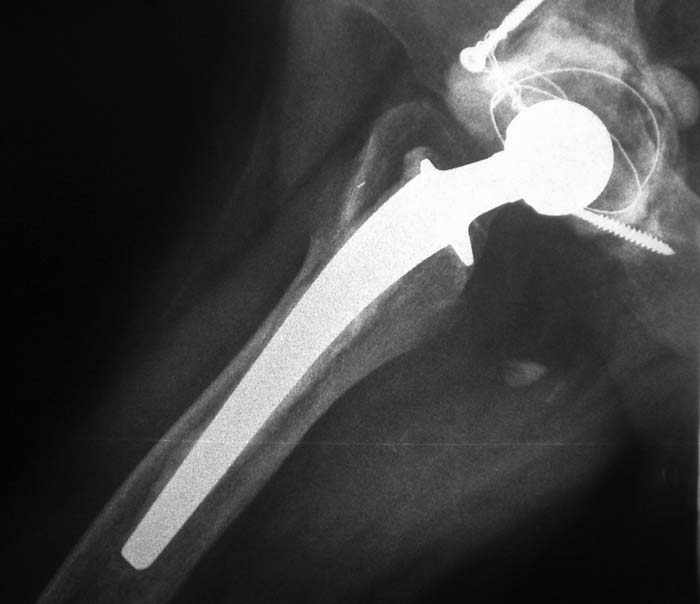

Мужчина, 45 лет. 6 мес. назад перенес тотальное эндопротезирование правого тазобедренного сустава по поводу ложного сустава шейки бедра.

Характер реконструкции вертлужной впадины не известен. Через 3 мес. после операции отметил щелчки и хруст при движениях в области эндопротеза. В анамнезе туберкулез легких. Сейчас, по заключению фтизиатра, в легких активного процесса нет. Местного воспаления нет.Предполагается нестабильность чашки в связи с бактериальным воспалением. Планируется удаление чашки и цемента, пластика дна измельченными аутотрансплантами и гидроксилапатитной керамикой, затем кольцо Мюллер, цементная чашка.

Смущает и ножка - зона просветления вокруг мантии. Предложения по тактике?

прямо скажем, очень загадочная конструкция с проволокой и винтами. :) На основании чего Вы подозреваете септическую нестабильность? Каковы результаты анализов? Согласен с доктором - нужно сделать пункцию. Есть ли снимки до и сразу после операции? Знаете ли Вы диаметр головки,какой будет внутренний диаметр Вашей чашки? Известно ли, чей протез? Может есть смысл найти автора работы и узнать о подробностях установки протеза?